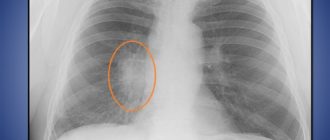

Возможен рак лёгкого

Прогноз выживаемости рака легких на 3 стадии: что нужно знать Сам по себе рак